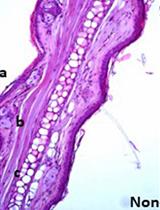

Representative data